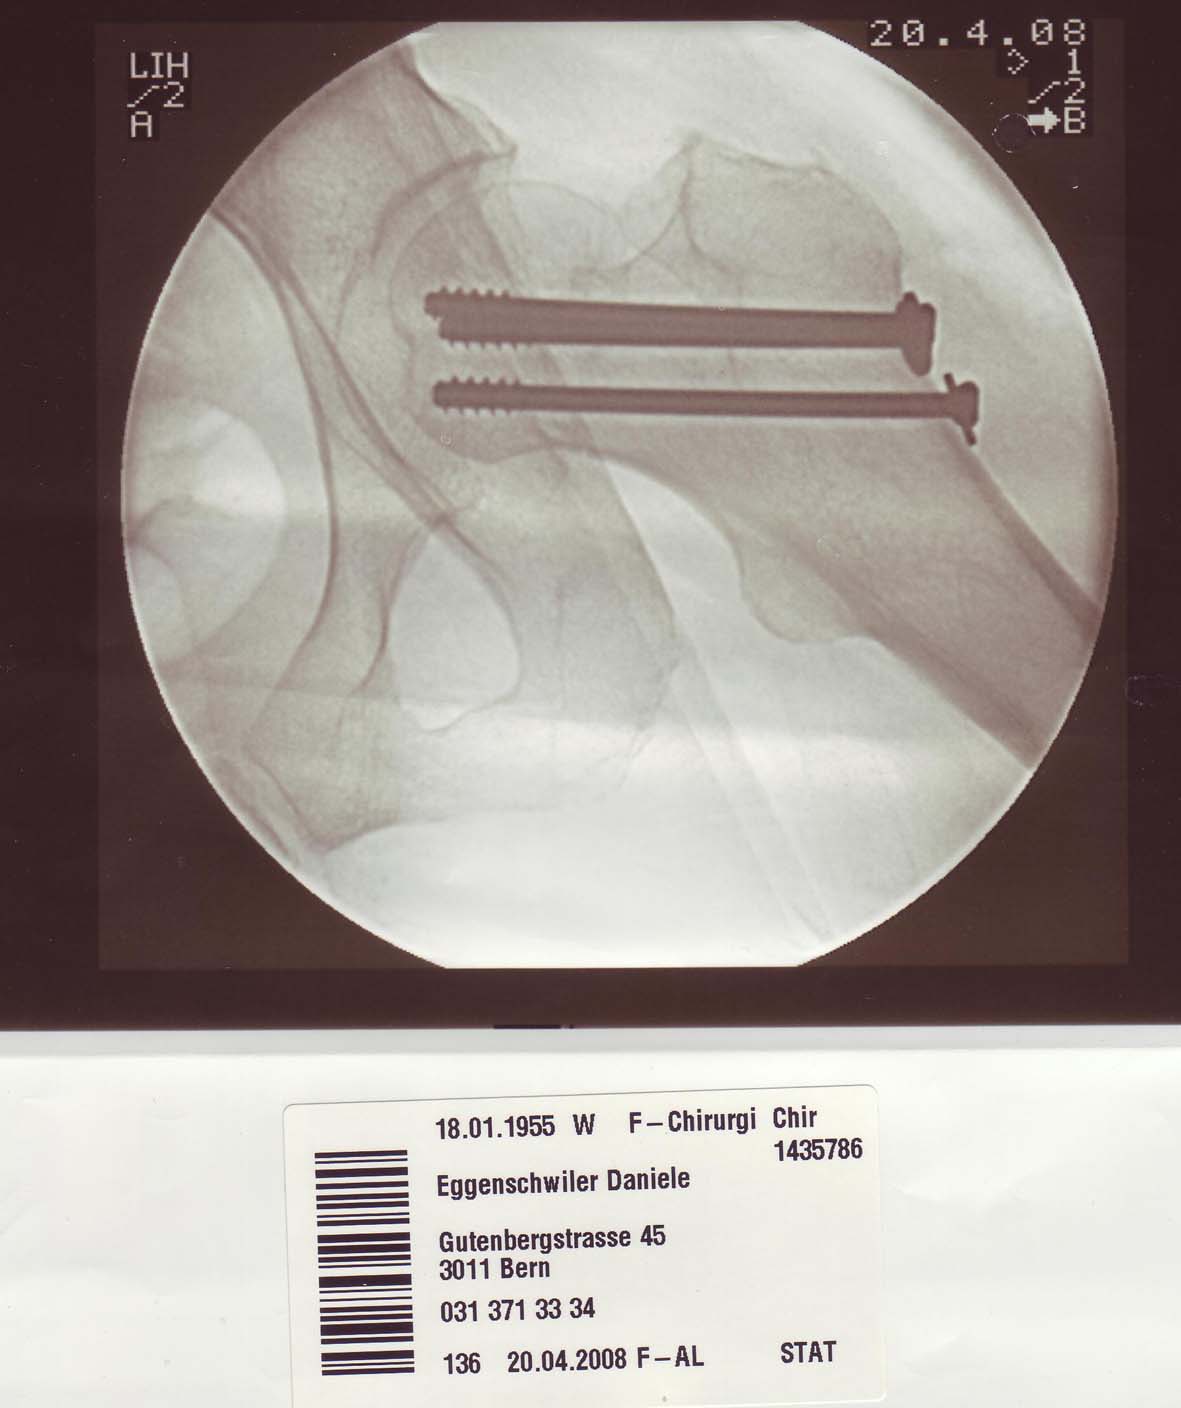

Am 20.4.2008 bekam ich ein besonderes Piercing verpasst:        back